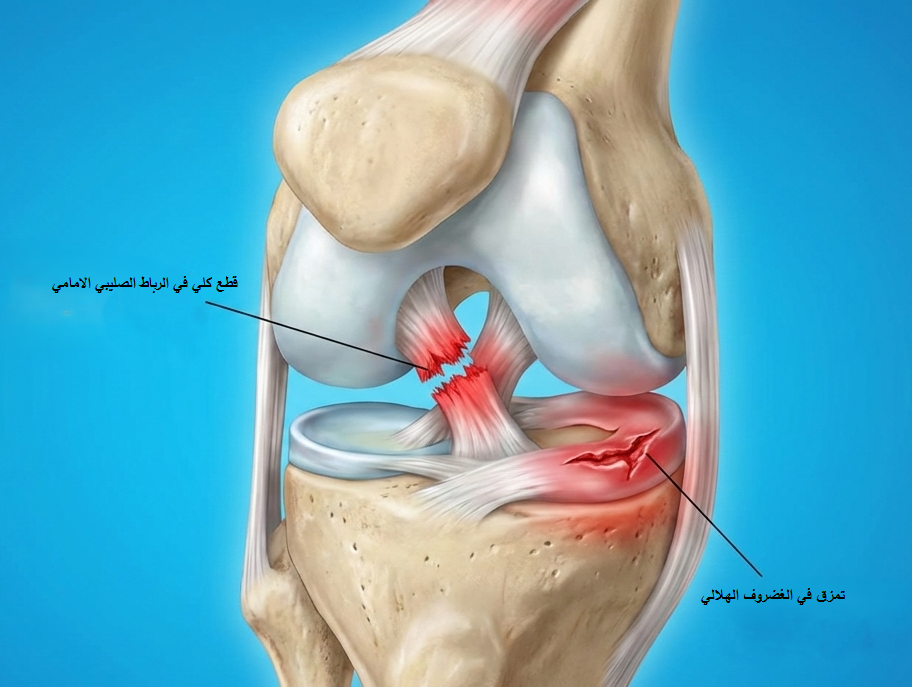

تمزق الرباط الصليبي: الأسباب والأعراض وطرق التشخيص الدقيقة

الرباط الصليبي الأمامي هو أحد أهم الأربطة داخل مفصل الركبة، ووظيفته الأساسية منع انزلاق عظمة الساق للأمام وضبط الحركات الدورانية أثناء الجري أو تغيير الاتجاه.

عند حدوث تمزق الرباط الصليبي، يفقد المفصل جزءًا كبيرًا من ثباته، خاصة أثناء الحركات المفاجئة، مما يؤدي إلى إحساس بعدم الاستقرار قد يتكرر مع النشاط البدني.

الركبة ليست مجرد مفصل بسيط، بل نظام ميكانيكي دقيق، وأي خلل في أحد عناصره – مثل الرباط الصليبي – ينعكس على الأداء الوظيفي بالكامل.

هذا بالاضافة إلى حتمية حدوث مضاعفات وإصابات أخرى في الركبة في حالة إهمال علاج قطع أو تمزق الرباط الصليبي الأمامي.

الفرق بين قطع وتمزق الرباط الصليبي

- التمزق قد يكون جزئيًا، أي أن بعض ألياف الرباط ما زالت سليمة

- اما القطع فيعني انفصال الرباط بالكامل وفقدان وظيفته تمامًا

الدقة في هذه المرحلة تمنع إغفال إصابات الغضروف الهلالي أو الأربطة الجانبية، والتي تؤثر بشكل مباشر على نتائج العلاج.

مضاعفات إهمال تمزق الرباط الصليبي

إهمال علاج تمزق الرباط الصليبي قد يؤدي إلى:

- تكرار عدم ثبات الركبة (خيانة الركبة)

- تمزق الغضروف الهلالي

- خشونة الركبة المبكرة

- تدهور تدريجي في الأداء الحركي

- ألم مزمن